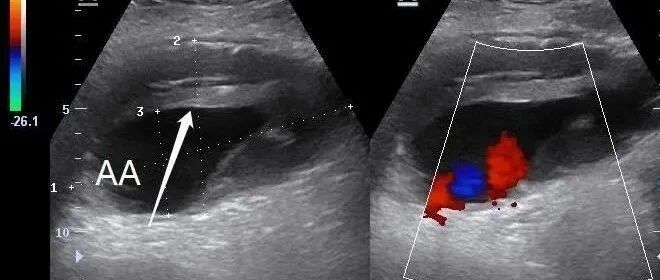

急诊床旁彩超诊断腹主动脉瘤破裂 2 例 丁香园超声时间 · 公众号 · 医学 · 1 年前 · |